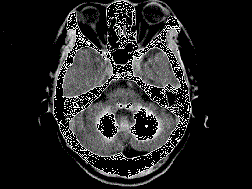

问题 男,49岁,反复发作性癫痫,双手震颤5年,伴头昏行走不稳,生化检查:血清钙降低,血清磷升高,请根据所提供图像,选择最可能的诊断 ( )

选项 A、肝豆状核变性 B、甲旁低 C、一氧化碳中毒性脑病 D、霉变甘蔗中毒 E、Fahr病

答案 B